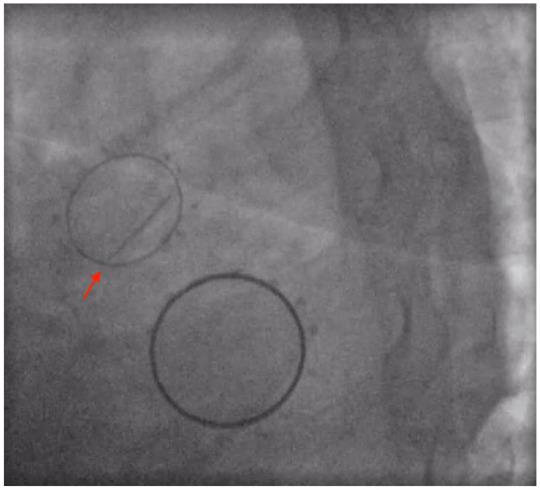

The incidence of mechanical valve thrombosis (MVT) is around 0.4 per 100 patient-years. Mitral valve thrombosis has a higher incidence than aortic valve thrombosis with a nearly 5-fold increase. Various factors contribute to MVT. The most common cause of valve thrombosis is poor adherence/disruption of anticoagulation therapy. Low cardiac output is known to increase the risk of prosthetic valve thrombosis. Other factors such as diabetes, hypertension, and other patient comorbidities might also play a role. Decreased flow promotes hypercoagulability. Lower pressure in the left atrium (and higher velocities in the left ventricle) can partially contribute to the higher incidence of mitral MVT versus aortic MVT. The presenting symptoms usually depend on the severity of the valve thrombosis; nonobstructive valve thrombosis patients have progressive dyspnea, signs of heart failure, and systemic embolization with strokes being the most common complication. In this article, we present a case of a middle-aged woman with a history of mitral and aortic mechanical prosthesis who presented with an ST-segment elevation myocardial infarction and pulmonary edema due to mechanical aortic valve prosthesis thrombosis. She had an isolated mechanical aortic valve prosthesis thrombosis with intact mitral valve, which, to the best of our knowledge, has not yet been described. We performed a literature review by searching PubMed and Embase using the keywords "mechanical valve," "thrombosis," "aortic," and "mitral," our search did not show similar cases.

机械瓣血栓形成(MVT)的发生率约为每 100 患者年 0.4 例。二尖瓣血栓形成的发生率高于主动脉瓣血栓形成,几乎增加了 5 倍。多种因素导致 MVT。瓣膜血栓形成最常见的原因是抗凝治疗的依从性差/中断。已知低心输出量会增加人工瓣膜血栓形成的风险。其他因素,如糖尿病、高血压和其他患者合并症,也可能起作用。血流减少会促进血液高凝。左心房压力降低(左心室速度升高)可能部分导致二尖瓣 MVT 与主动脉 MVT 的发生率较高。临床表现通常取决于瓣膜血栓形成的严重程度;非阻塞性瓣膜血栓形成患者逐渐出现呼吸困难、心力衰竭体征和全身性栓塞,其中中风是最常见的并发症。在本文中,我们报告了 1 例中年女性,有二尖瓣和主动脉机械假体的病史,因机械主动脉瓣假体血栓形成而出现 ST 段抬高型心肌梗死和肺水肿。她患有孤立性机械主动脉瓣假体血栓形成,二尖瓣完整,据我们所知,这种情况尚未被描述。我们通过在 PubMed 和 Embase 上使用关键词“机械瓣”、“血栓形成”、“主动脉”和“二尖瓣”进行了文献回顾,我们的搜索没有显示出类似的病例。